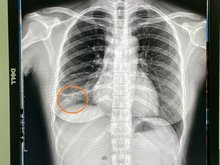

【新唐人亞太台 2022 年 02 月 17 日訊】近日台灣的中共肺炎Omicron呈現急速擴大流行的趨勢,引發民眾的高度關注,然而人們卻不知,仍有另一種傳染性疾病依然悄悄在進行散播。烏日林新醫院胸腔內科主治醫師許人文近日在門診發現一名32歲女作業員,已經咳嗽兩三個月不見好轉,卻遲遲未就醫,來門診進行胸部X光檢查,發現右下肺葉有一小片扁平塌陷和浸潤的病灶,醫師先投以抗生素治療,同時幫她收集痰液化驗結核菌,竟然發現痰液中佈滿了密密麻麻的肺結核菌,屬於罕見的「右下肺葉」開放性肺結核病人,醫院已進行法定傳染病通報。

根據國外文獻統計,下肺葉肺結核的病人,大多以40歲以下的年輕女性為主,肺結核的X光表現,大部分都是在兩側的上肺葉,然而在「下肺葉」的個案非常少見,常常只有零星個案被報導,也因此常常會被醫療人員所忽略,再加上肺結核具有「非立即性傳染、不易診斷」之特性,醫師初步需要先排除肺炎、肺膿瘍、或是肺癌,再進一步考慮是否為肺結核的可能性!